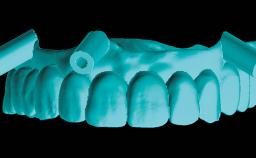

Professor of the Department of Prosthodontics